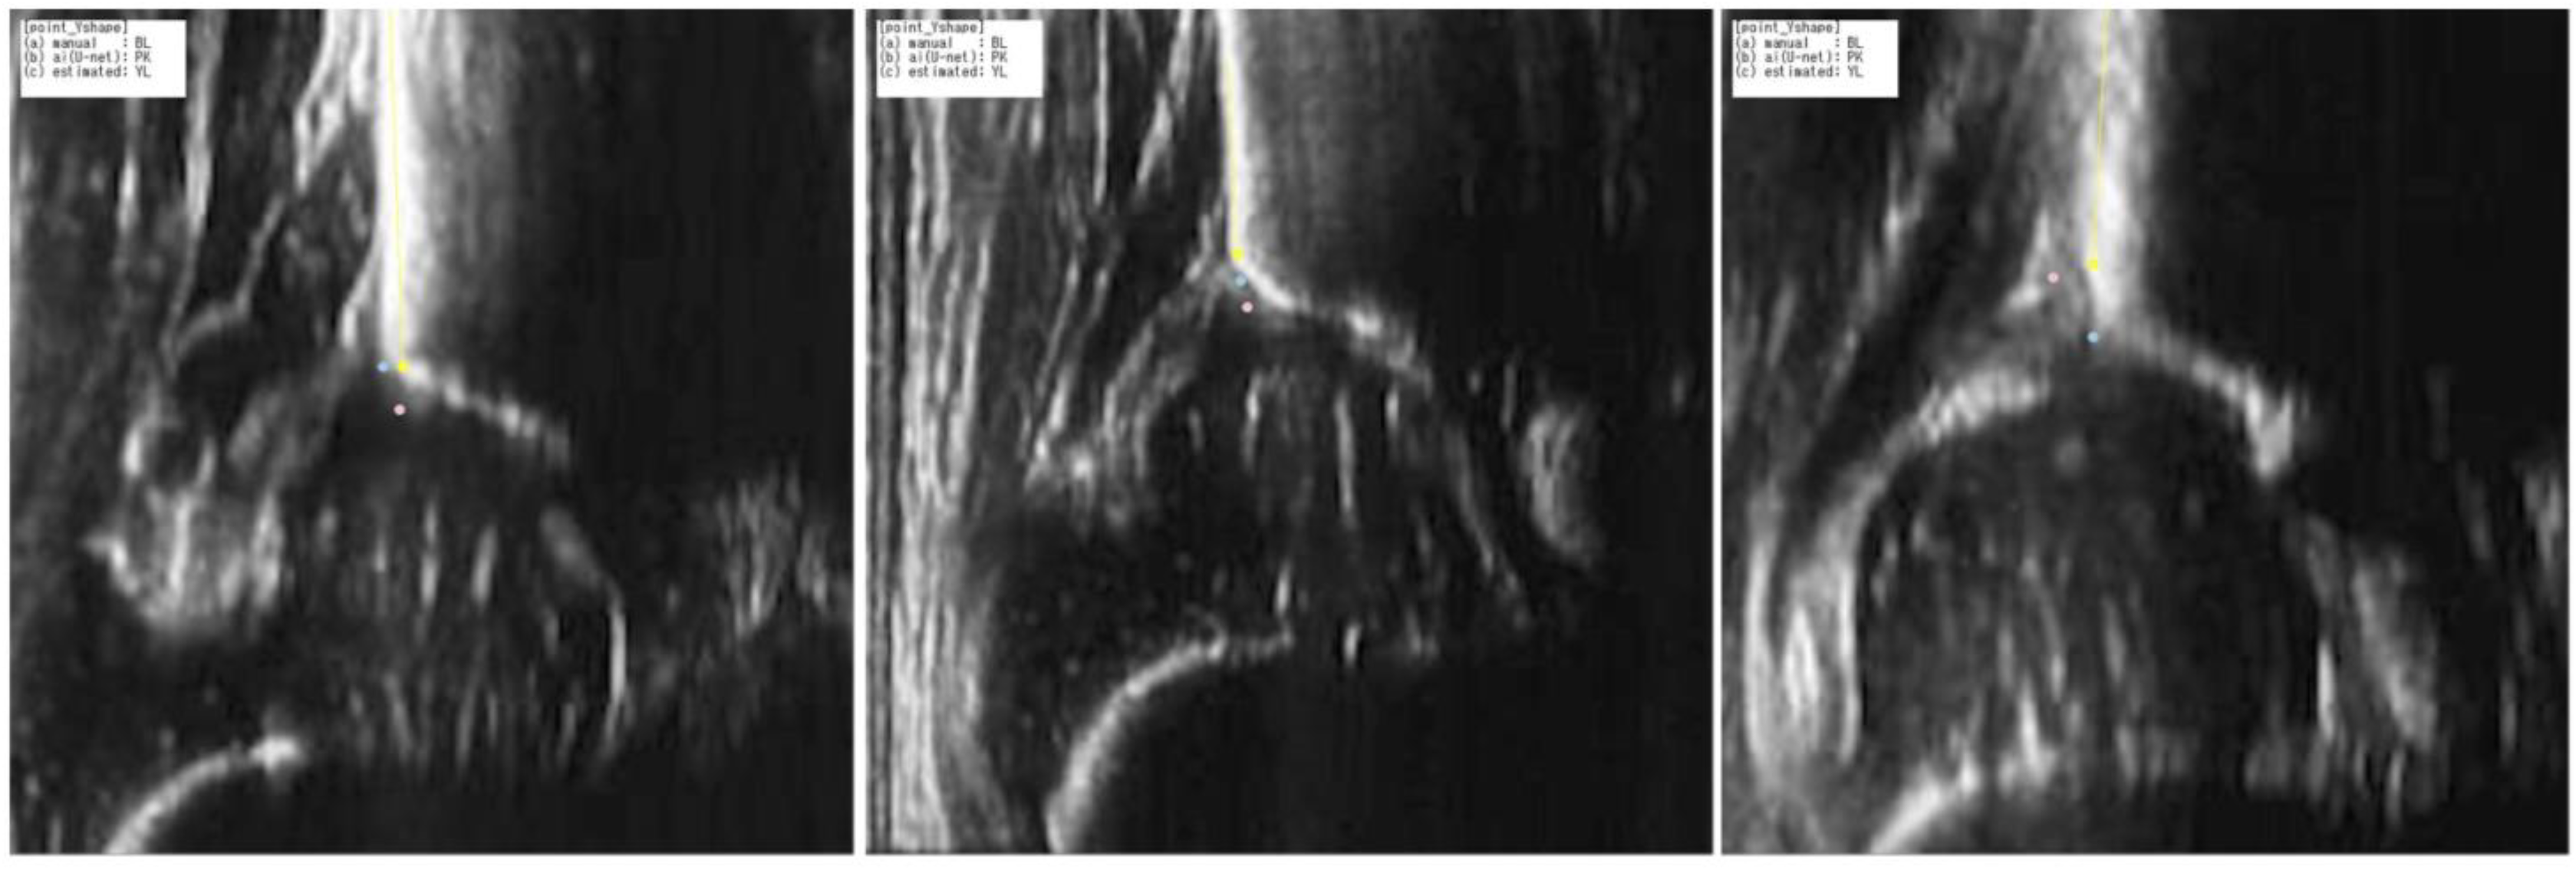

2.3.1. Apex Point Estimation

3.1. Step1: Accuracy of the Estimated Apex Point